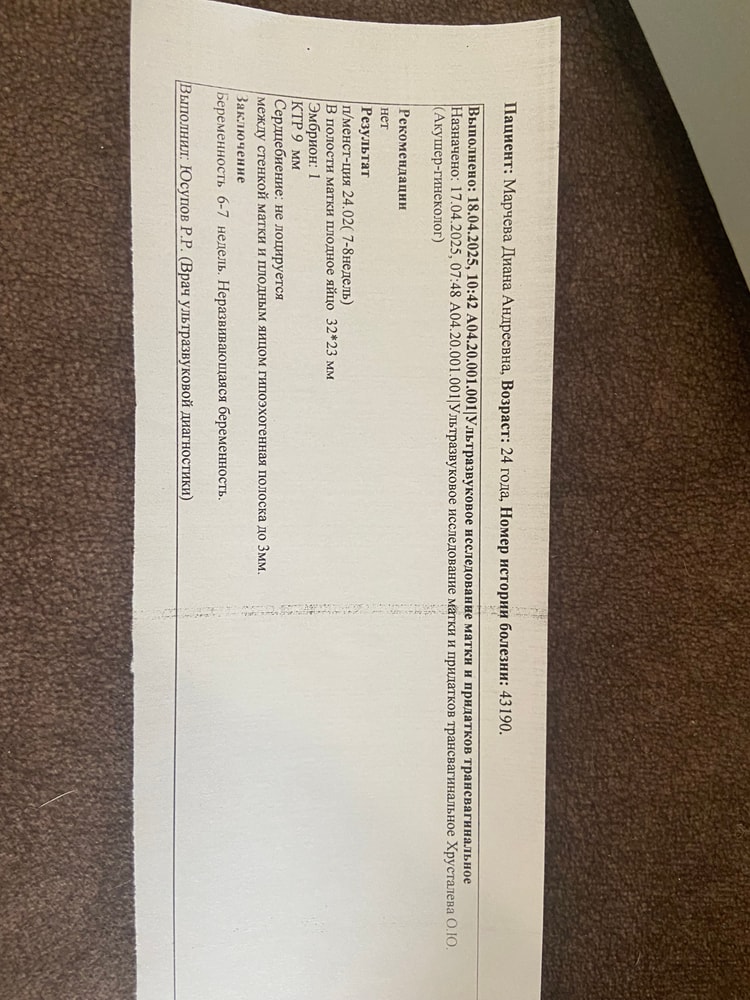

Лежала на сохранении, так как 14 апреля по узи сказали что есть отслойка. 18 апреля сделали узи, сказали Эмбриональный срок 4-5 недель. Эмбрион растет. 14 апреля эмбрион был 6,3, а вчера 18 апреля эмбрион уже 9.

сердцебиения не могут расслышать. Под вопросом не развивающаяся.

думаю просто рано они делают выводы. Слышала что у многих сердцебиение только в 8-9 недель прослушивается. И если была бы не развивающаяся беременность, я так понимаю то эмбрион бы и не рос?

узи за 14 апреля и 18 апреля прикрепляю.